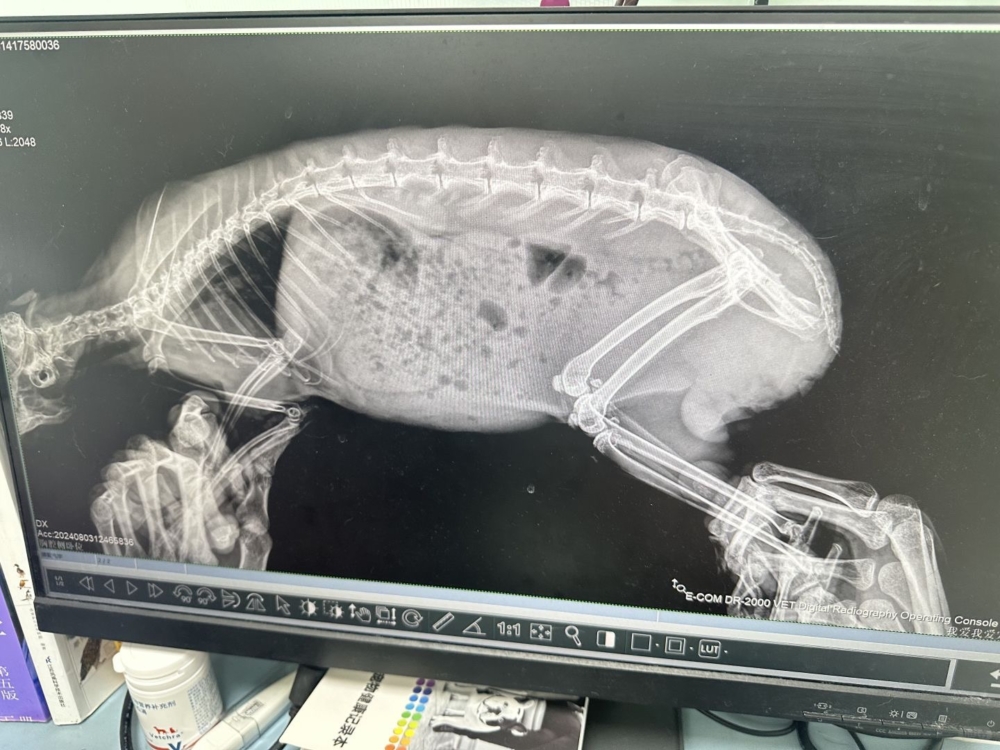

一旦懷疑有腸胃停滯,獸醫會進行全面檢查來確認診斷,可能包括觸診腹部、拍攝X光以評估停滯的嚴重程度,以及進行血液檢查以檢查潛在的病因~